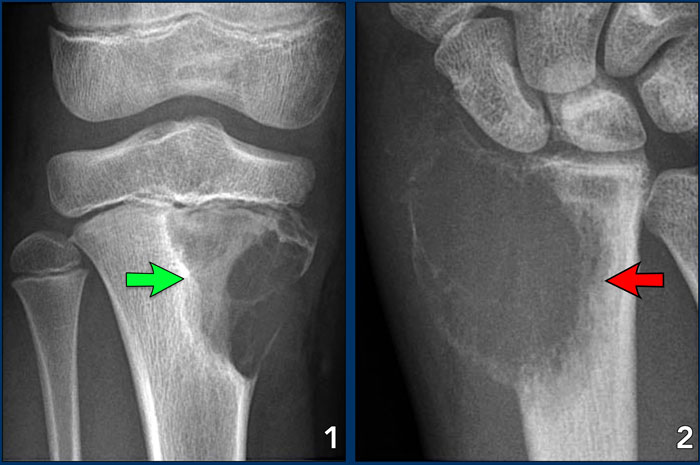

- X-rays: To identify any abnormalities in the bone structure.

- MRI/CT/PET Scans: To provide detailed images of the bone and surrounding tissues.

4. Osteochondroma

- Description: A benign tumor that forms a bony outgrowth on the surface of a bone.

3. Chondroblastoma

- Description: A rare benign tumor that typically occurs at the ends of long bones near the joints.